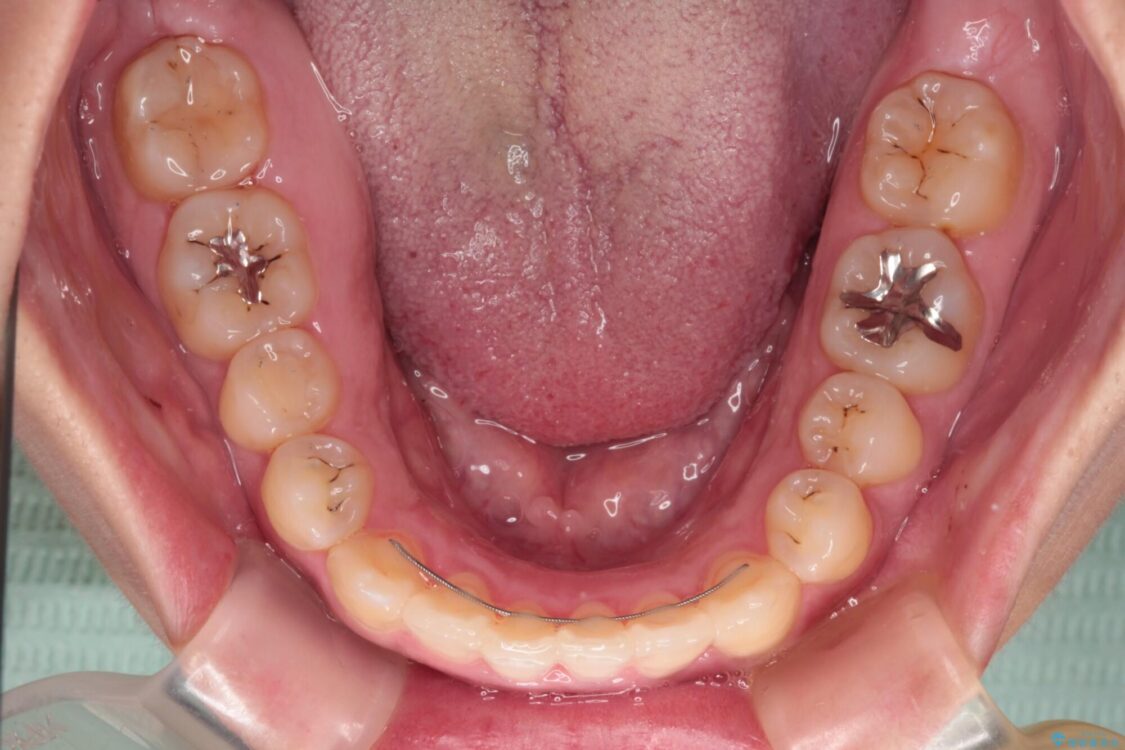

前歯の叢生と八重歯を気にして来院された患者様です。

治療途中

• 【モニター】カリエール・ディスタライザーを併用した八重歯のインビザライン矯正 治療途中画像